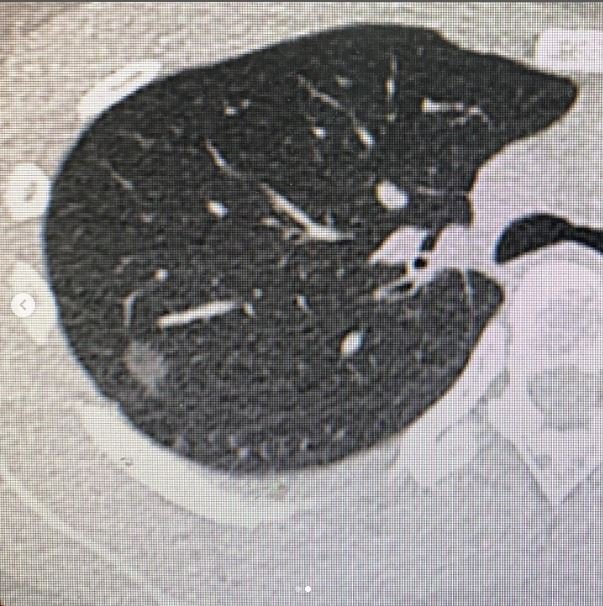

臺北醫院護理師雅薇日前剛入選全台最正的8位白衣天使,沒想到近期卻傳出罹癌的噩耗,她表示自己這半年來偶爾咳嗽加上長期偏頭痛,因此決定健檢多花8000元加做低劑量肺部電腦斷層(LDCT),沒想到竟意外發現罹患肺腺癌,她崩潰在文中喊道:「我才30歲,為什麼會得『肺癌』?不煮飯不菸不酒,家族沒有人肺癌」

雅薇表示在照LDCT的當下就用電腦看到一顆充滿敵意的結節,「我很緊張馬上打給我的胸內、外主任幫我看片子,胸外醫師說:『這一顆...感覺不太好』,胸內主任看了很久難以啟齒,被我逼問之下才脫口:這可能惡性....」當天雅薇是哭著上班的,護理師們打電話來報告病人狀況,她只能一邊流淚一邊處理工作

後來雅薇幸運轉介到台大癌醫團隊,陳晉興副院長看完片子和善表示:「80%是惡性,但你放心我幫你開刀處理,我保證不會轉移!」前幾天她也完成了胸腔鏡肺腫瘤併淋巴廓清切除手術,目前確定是肺腺癌第一期,癌醫腫瘤內科專科護理師學姐來探視時分享,很多腫瘤內科的患者都是第三或第四期,他們都正努力投藥治療,甚至回到職場工作,以現在台灣醫療的進步程度他們都有機會看到自己孩子畢業。

雅薇也轉念表示:「我想...在30歲能提早發現已經很幸運,如果今年沒有自己加做LDCT,就算每年X光檢查也看不到(X光能看到,可能已經末期),謝謝我很重要的朋友,她常常提醒我要記得健康檢查,催促我要保好保險(雙實支、重大傷病真的很重要)」健康檢查時護理師、醫師看到她的年紀都好奇「怎麼會想到要做這個檢查?」